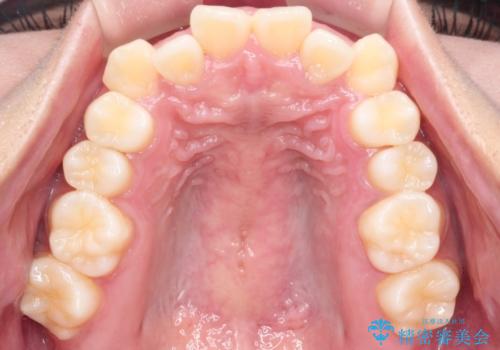

【インビザライン】笑ったときに目立つ八重歯をなおしたい

- 笑ったときに八重歯が見えることを主訴に来院されました。

下の前歯が一本足りない患者様でしたので、シミュレーションを作り、事前に患者様と治療ゴールのイメージをしっかり共有したうえでインビザラインを用いて治療を行っています。

奥歯を後ろのほうに動かすことで、前歯も少し下がることができ、矯正後の口元も満足していただきました。

下顎の前歯が一本ない場合は上下の正中は合いません。